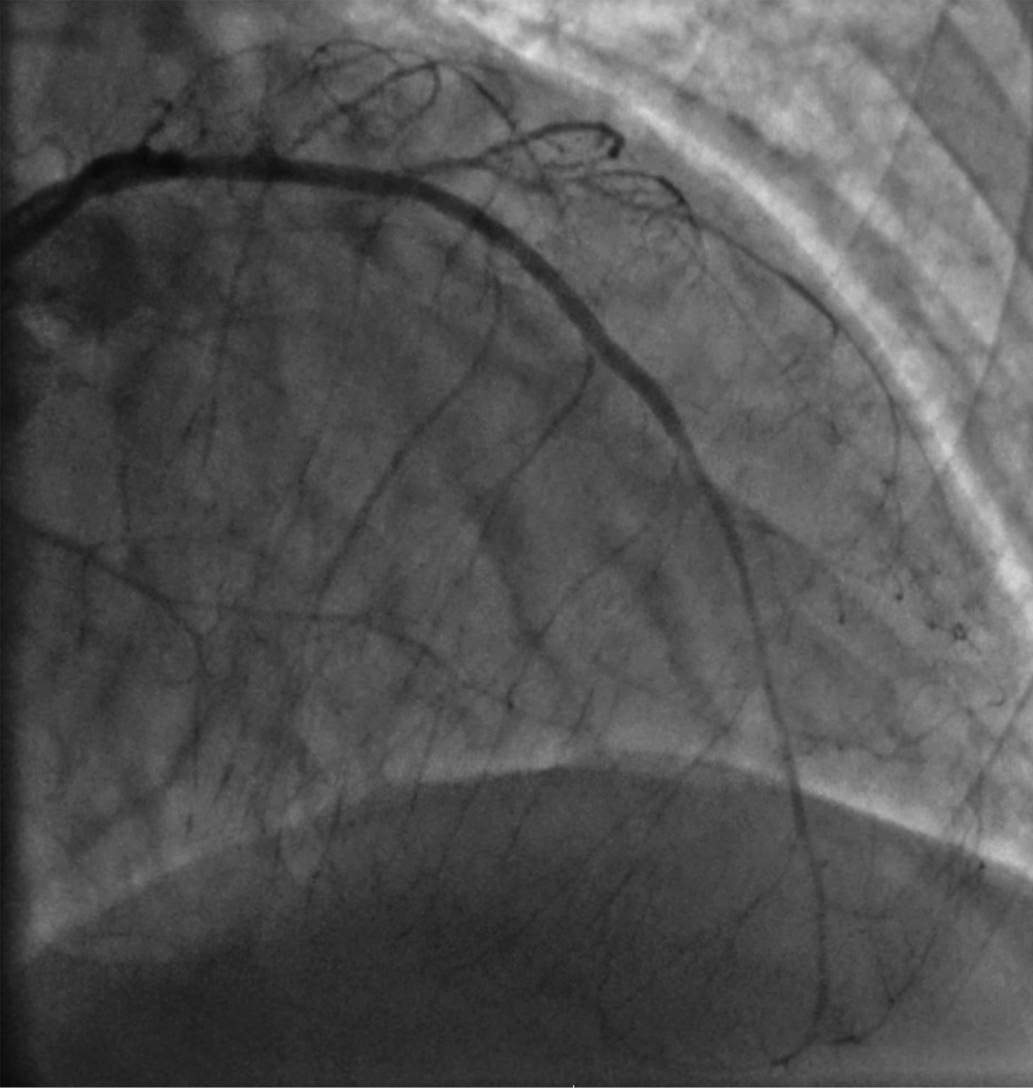

Вместе с тем причина выраженной систолической дисфункции ЛЖ оставалась неясна. Для уточнения ИБС как причины систолической дисфункции ЛЖ больному была проведена коронарография, на которой было выявлено: ствол левой коронарной артерии проходим; передняя межжелудочковая артерия (ПМЖА) — с диффузными изменениями на всем протяжении, малого калибра; стеноз в средней трети 70–90%; стенозы дистальной трети до 50%; диагональная артерия — малого калибра, тандемные субтотальные стенозы в проксимальной трети; огибающая артерия — неровные контуры проксимальной трети; 1-я ветвь тупого края (ВТК) окклюзирована в устье, малого калибра; постокклюзионные отделы контрастируются повнутрисистемным коллатералям; 2-я ВТК окклюзирована в проксимальной трети, малого калибра; постокклюзионные отделы контрастируются по внутрисистемным коллатералям; маргинальная ветвь — субтотальный стеноз в устье; правая коронарная артерия (ПКА) — неровные контуры проксимальной трети, окклюзия в средней трети; дистальные отделы контрастируются по внутри- и межсистемным коллатералям (рис. 1, 2).

Рисунок 1. Правая коронарная артерия.

Figure 1. Right coronary artery.